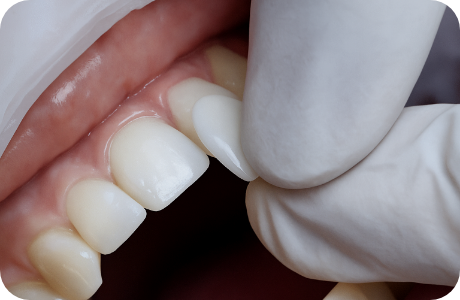

치아 삭제량을 줄여 치아 보존

오전 내원, 오후 부착 치료

얇고 투명한 투과율로 높은 심미성, 높은 강도를 자랑하는 리튬 다이 실리케이트 블럭을

이용하여 적은 치아 삭제로 이상적인 치아를 복원이 가능합니다.

두꺼울수록 치아 삭제량이 많아지는 기존의 방식을 보완한

매우 얇고 치아에 잘 맞는 0.1mm 두께 보철로 자연스러운 라미네이트를 진행합니다.

심미보철 진행 후 가장 걱정되는 부분인 변색 부분에서도,

치료 이후 변색과 착색이 적어 오랫동안 높은 지속성을 경험하실 수 있습니다.